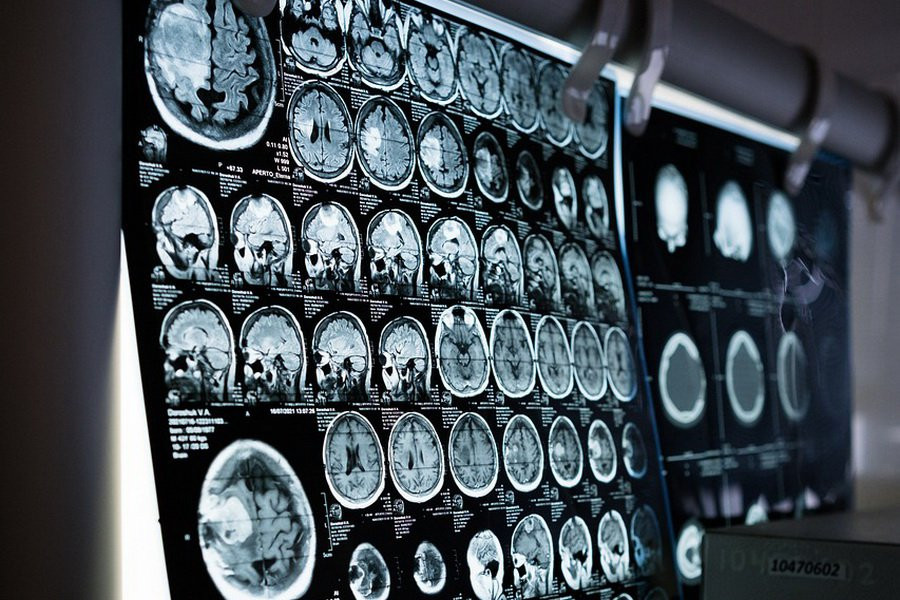

Фото из открытых источников

Исследователи из Соединенных Штатов разработали инновационную систему адаптивной глубокой стимуляции мозга. Эта разработка, созданная нейрофизиологами, способна самостоятельно отслеживать изменения в работе мозга пациентов и корректировать режим стимуляции для максимально эффективного подавления симптомов заболевания. Информация об этом достижении была опубликована пресс-службой Университета Калифорнии в Сан-Франциско (UCSF).